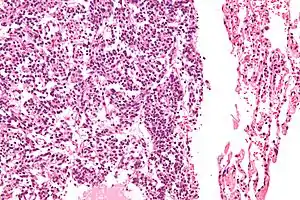

Micrograph of a typical pulmonary carcinoid tumour.

The definitive diagnosis is rendered by a microscopic examination, after excision. Typical carcinoids have cells with stippled chromatin and a moderate quantity of cytoplasm. They typically have few mitoses and lack necrosis. By definition, they are greater than 4 mm in largest dimension; smaller lesions are referred to as pulmonary carcinoid tumourlets.